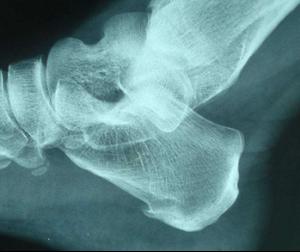

跟骨骨刺主要表现为站立或走路时间久了,足跟会产生疼痛,走路时路面不平或踩到石子时则会产生剧烈疼痛。多由长期劳累、气血瘀滞、筋骨失养、经络不通所致。

中老年人足跟痛多是跟骨骨刺引起,其表现除疼痛外,还可能伴有局部肿胀,夜间疼痛,早晨脚跟不能着地,需要用手按摩一段时间,才能慢慢着地。严重影响生活和劳动能力。除了用上方外,也可以不用陈醋,单用威灵仙400克,煎取药液600毫升,每天熏洗患侧足跟2次,每次半小时,15天为1疗程。